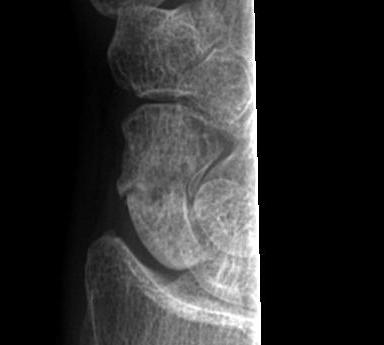

Injury progresses from radial to ulna

- usually disruption proximal row either side of lunate

1. Capitate usually displaces dorsally initially

- volar lunate dislocation is end stage

Convincing association with development of osteoarthritis

- arthritic changes beginning at radial styloid

- progress to scaphocapitate & capitolunate